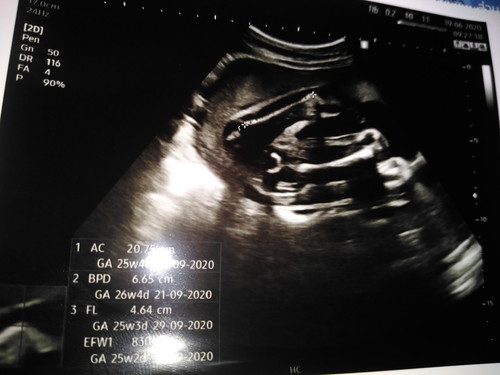

ลักษณะเเบบนี้ ผช.หรือผญ.ค่ะ😂😂😂

น่าจะหญิงจ้า

หญิงจ้า